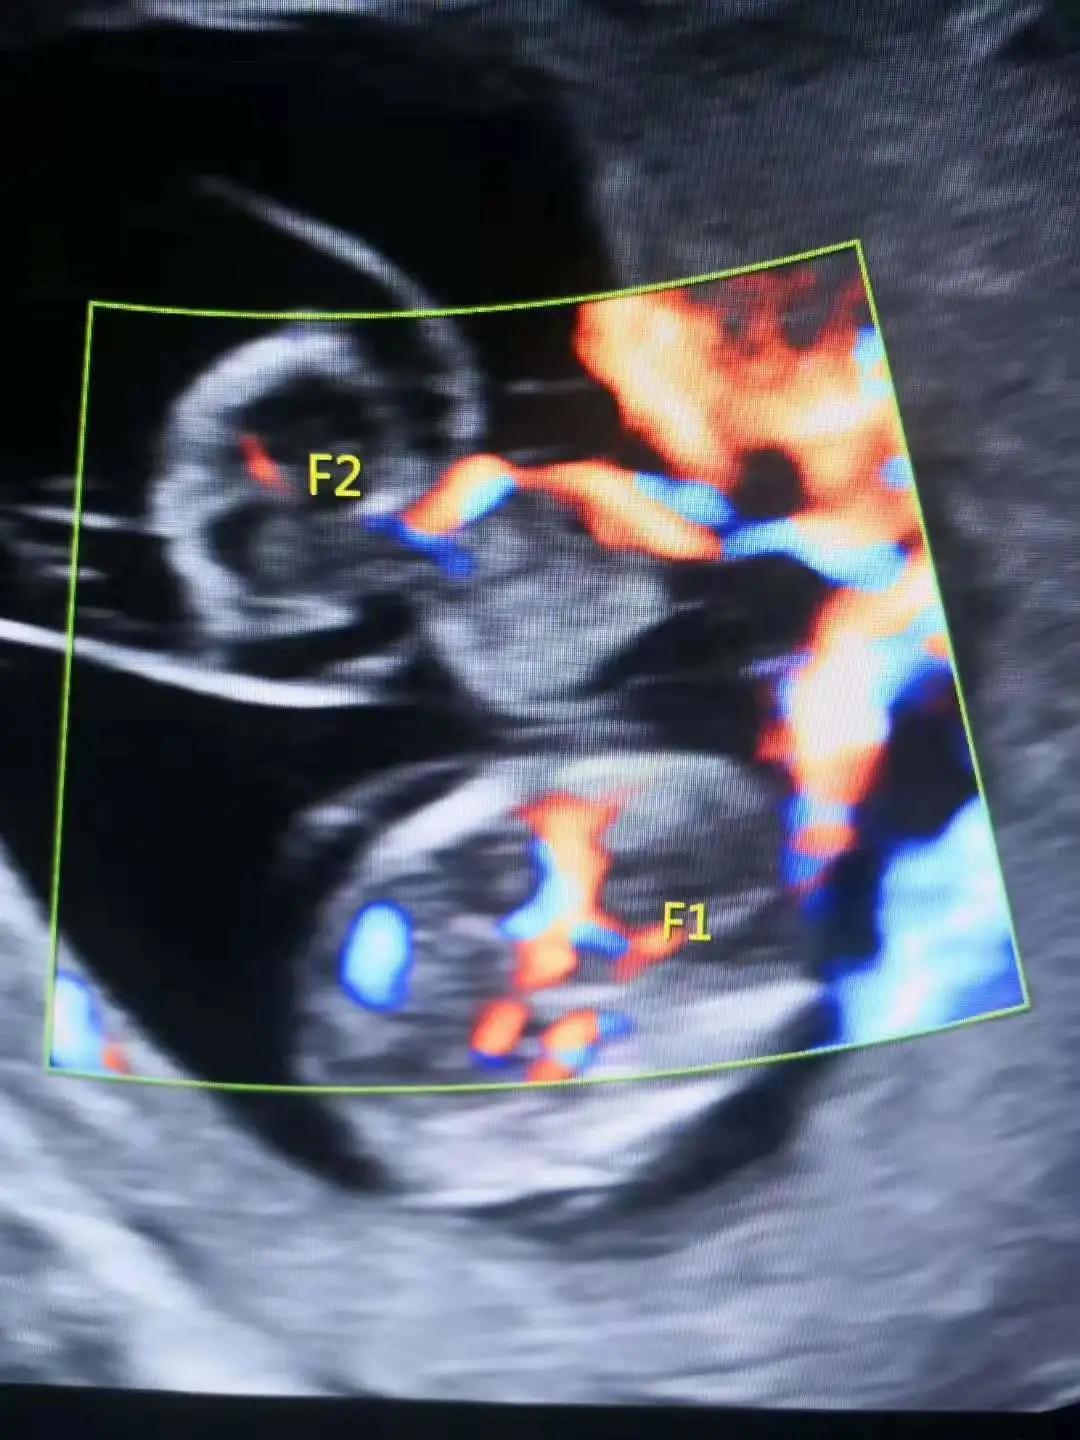

(双胎反向动脉灌注序列征超声图)